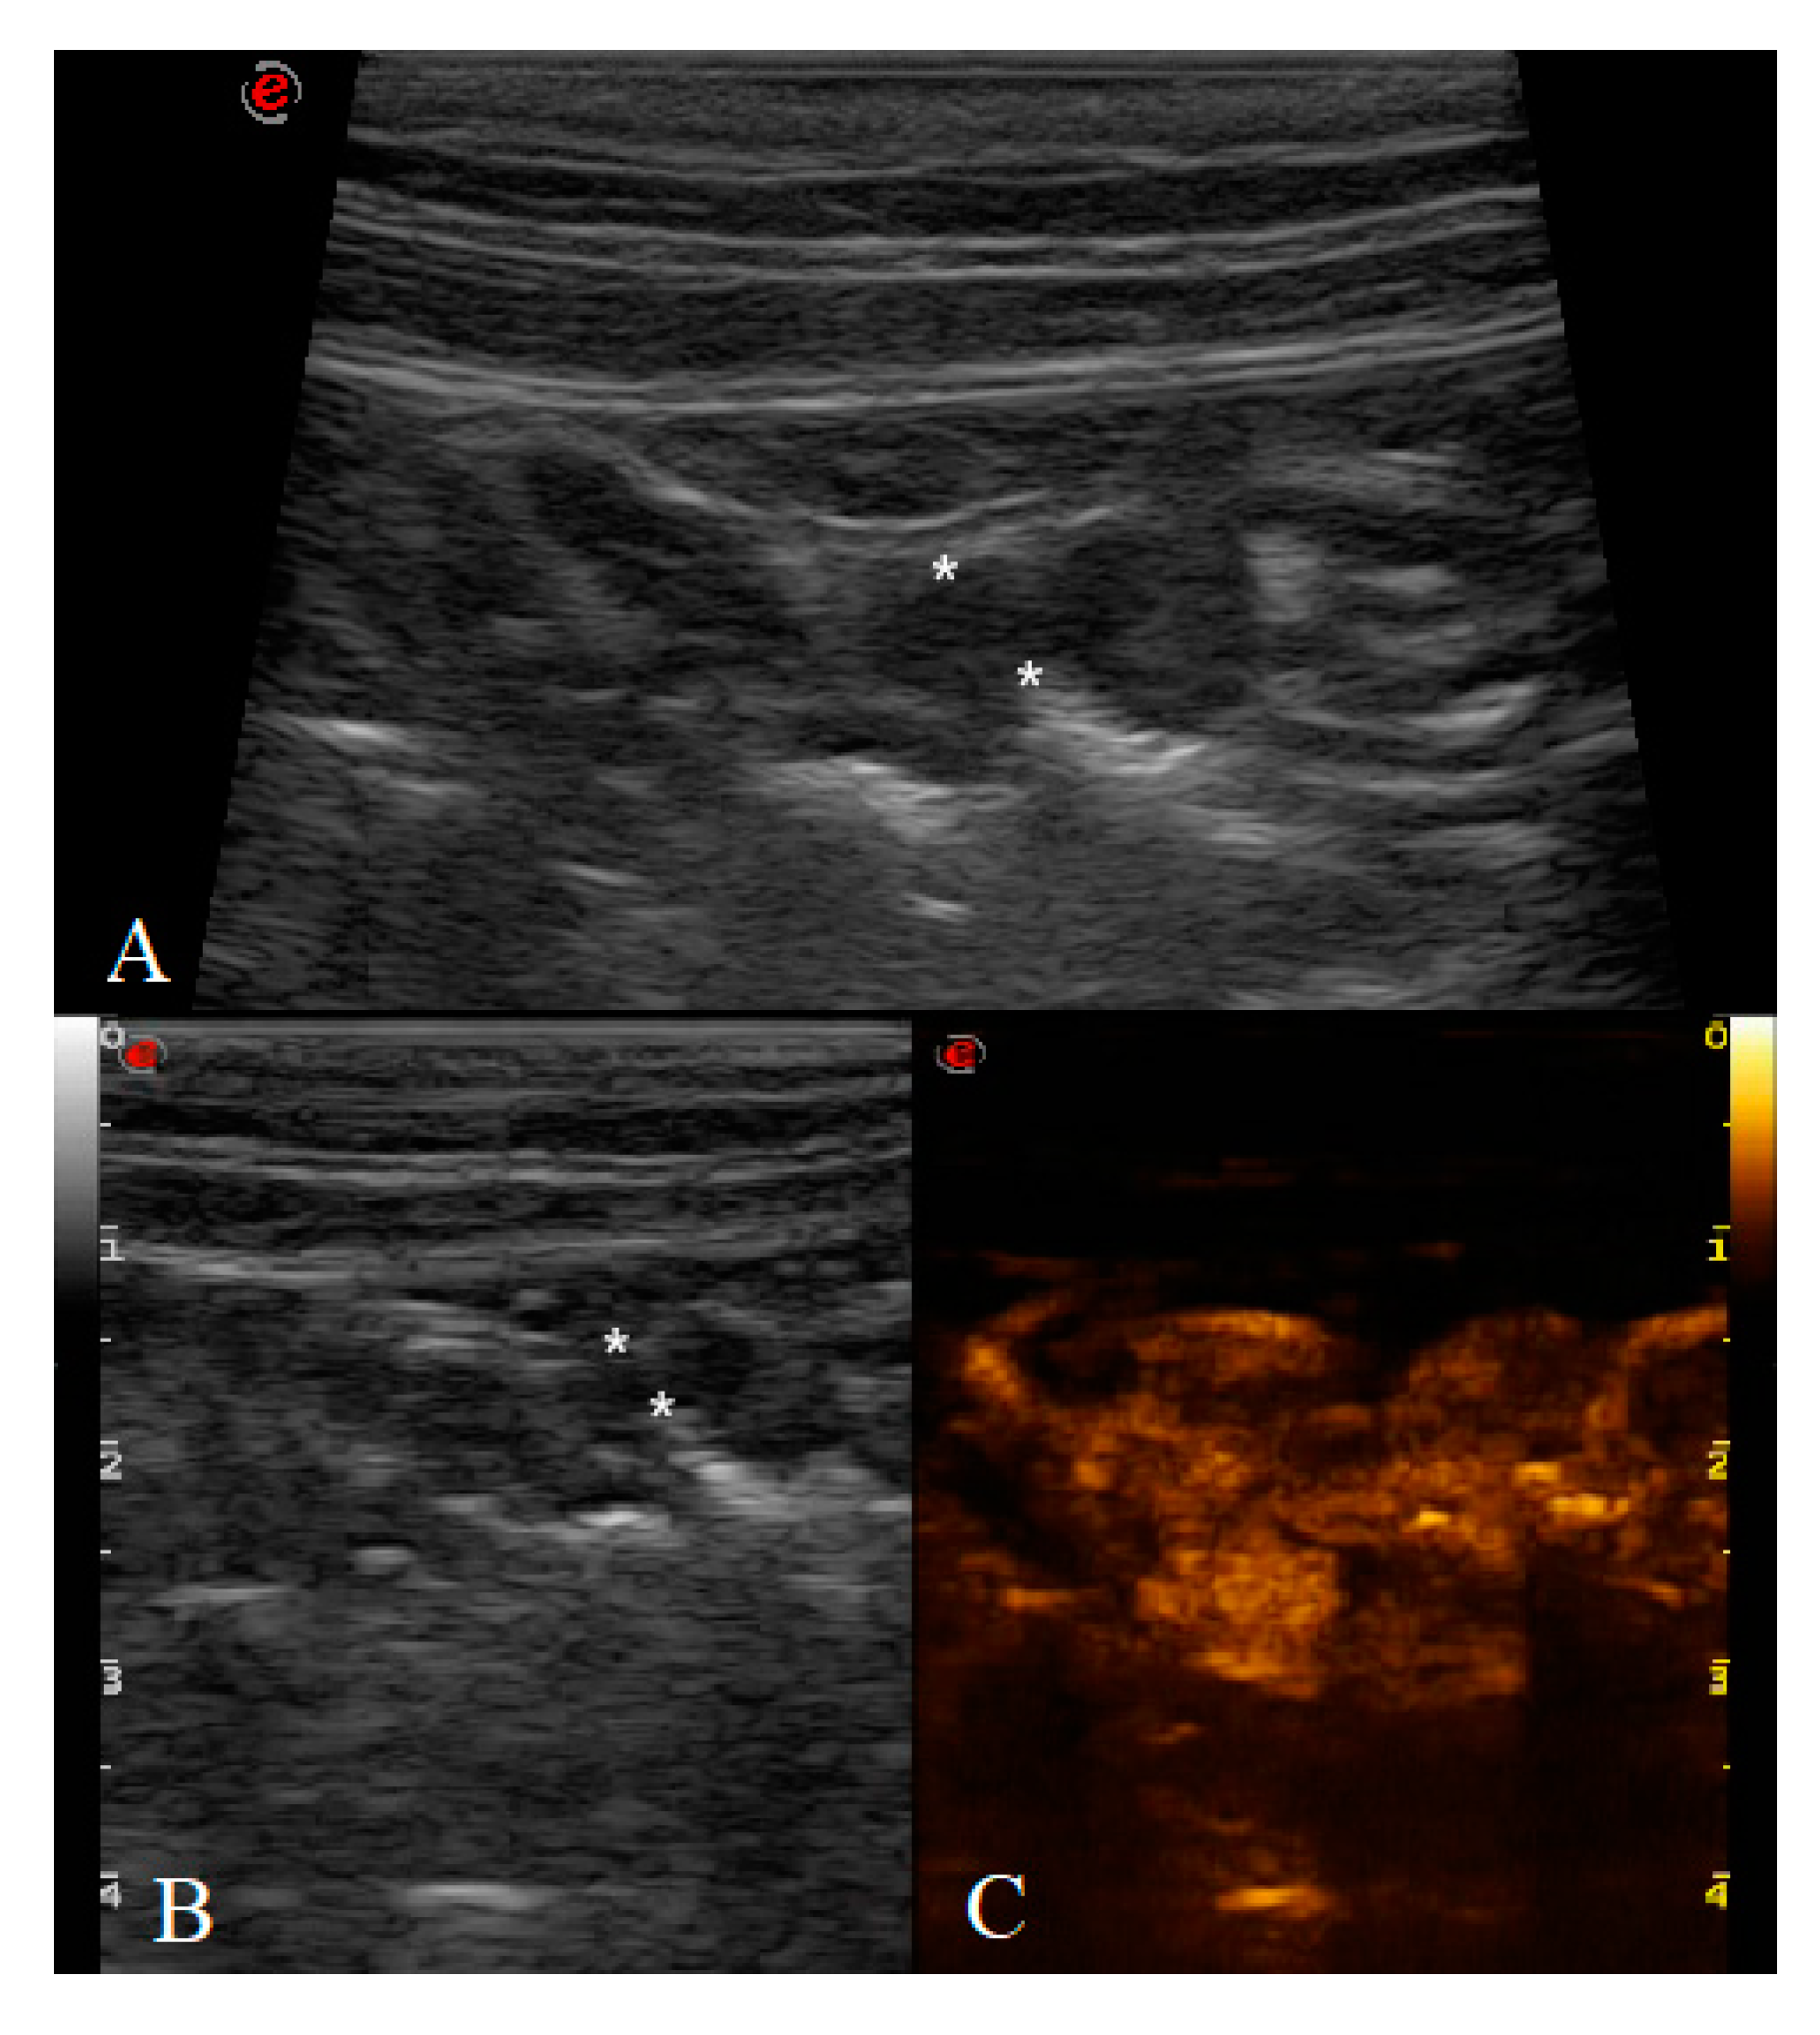

Between 2017 and 2020, a total of 31 cats underwent B-mode US and CEUS examination. Two cats were excluded because of the poor clip’s quality obtained from the CEUS examination and quantitative analysis could not be performed. All the gastric neoplasms were confirmed by cytological, histological and/or immunohistochemical diagnosis as lymphoma divided in LGAL and HGAL. No adverse effects were noted in any of the patients. A total of 29 cats were included in the study: six healthy (HEA) cats in the control group (mean age 2.08 ± 0.5 years), nine in the inflammatory (INF) group (mean age 6.4 ± 3.3 years), three in the LGAL group (mean age 12 ± 1 years) (Figure 2), and 10 in the HGAL group (mean age 9.4 ± 3.7 years) (Figure 3). All the HEA cats included in the control group were followed up on and checked 12 months after the first examination, confirming the absence of clinical and ultrasonographic signs of gastric disease.

Figure 2. Cat affected by gastric low-grade lymphoma (LGAL) showing: (A) diffuse reduced layer definition associated with mild increases in wall thickness (3.8 mm between the asterisks) on B-mode examination; (B,C) B-mode (B) and contrast-enhanced ultrasonography (CEUS) (C) clip acquired using dual-mode visualization in order to better identify the gastric wall during CEUS examination.